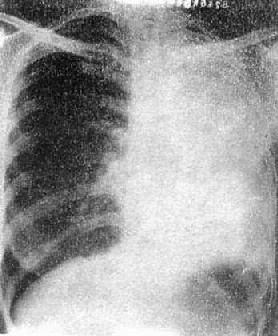

2)右肺中叶不张:较为常见,后前位表现为右肺下野内侧靠心右缘现上界清楚下界模糊的片状致密影,心右缘不能分辨(图3-1-9)。侧位上表现为自肺门向前下方倾斜的带状或尖端指向肺门的三角形致密影(图3-1-9)。上、下叶可有代偿性肺气肿。

右肺中叶肺不张(正、侧位)

图3-1-9 右肺中叶肺不张(正、侧位)